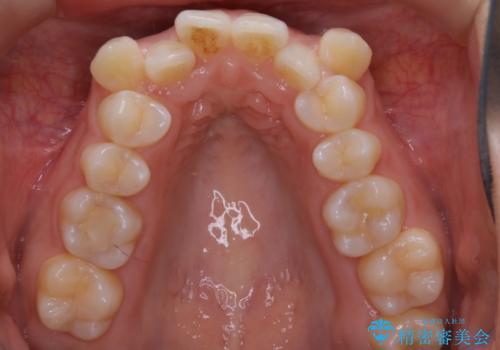

- 上顎の八重歯が気になるとのことで来院されました。

左側のかみ合わせは、歯1本分かみ合わせが前にずれていました。上顎左右の奥歯を2本抜歯しています。

下顎は、歯の側面を少し削ることで歯並びを整えました。

上顎と下顎の奥歯の抜歯(計4本)を行う治療方法もありますが、口元のバランスのことも考え、上顎の抜歯のみで、治療を行いました。

八重歯でがたつきは重度でしたが、きれいな歯並びにすることができました。